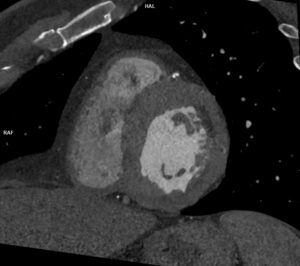

Figurile 2 si 3 reconstrucţii volumice aortă toracică

Video 2: valva aortică morfologic bicuspidă

Discuţie caz nr 86: Valva aortică este morfologic bicuspidă la 1% din populație și asociază, cu timpul, creștere de calibru a aortei ascendente datorită fluxului turbulent determinat de modificarea de morfologie a valvei aortice – în unele cazuri această malformație congenitală asociază modificare de calibru a aortei descendente proximal – coarctaţie de aortă.

DE LUAT ACASĂ!!! Valva aortică este bine vizualizată prin examinare CT atunci când achiziția imaginilor se face cu sincronizare cu semnalul ECG, de aceea toate solicitările de angioCT de aorta toracică se indică a se efectua cu sincronizare ECG pentru vizualizare și măsurători corecte alte tractului de ejecție a ventriculului stâng, vâlvei aortice și rădăcinii de aortă. În ultima perioadă este mare nevoie de aceste măsurători datorită apariției valvelor aortice și protezelor aortice ce pot fi implantate intervențional (TAVI / TAVR).